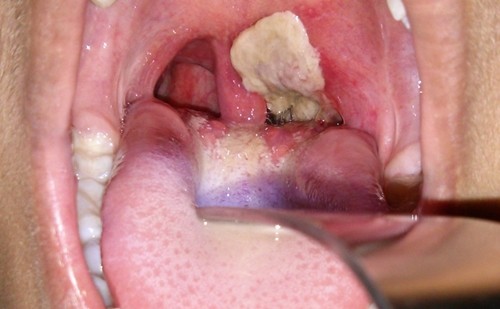

Bệnh nhân H’Si được đưa vào BV Đa khoa vùng Tây Nguyên cấp cứu trong tình trạng thở khò khè, họng có nhiều giả hạc trắng, bóc ra chảy máu vào ngày 29/8.

Đến 14h30 cùng ngày, bệnh nhân chuyển nặng, tiên lượng xấu, theo dõi bạch hầu. Đến khuya cùng ngày, bệnh nhân lên cơn khó thở, phản xạ kém, chẩn đoán bạch hầu thanh quản, suy hô hấp cấp độ 4. Lúc 1h40 ngày 30/8, người nhà xin về và tử vong trên đường về.

Bạch hầu là 1 bệnh truyền nhiễm cấp tính do trực khuẩn bạch hầu gây ra. Bệnh lây truyền qua đường hô hấp hoặc qua tiếp xúc trực tiếp với các dịch tiết từ niêm mạc mũi họng của bệnh nhân hoặc người lành mang trùng khi ho, hắt hơi.. Biểu hiện chính là viêm họng, thanh quản và có thể có biến chứng nặng do ngoại độc tố. Bệnh có thể gặp bất cứ mùa nào, nhiều ở tháng 8-9-10, xuất hiện chủ yếu ở trẻ em 1-10 tuổi, nhưng có thể gặp ở người lớn nếu không có miễn dịch. Bệnh có thể gây thành dịch. Bệnh xuất hiện khi có tình trạng nhiễm trùng ở đường thở trên hay vùng mũi hầu tạo nên lớp màng xám, mà khi hiện diện tại vùng thanh quản hay khí quản, có thể gây ra thở rít và tắc nghẽn. Bị ở mũi có thể làm trẻ chảy máu mũi. Độc tố bạch hầu gây liệt cơ, viêm cơ tim, dẫn đến tử vong. |